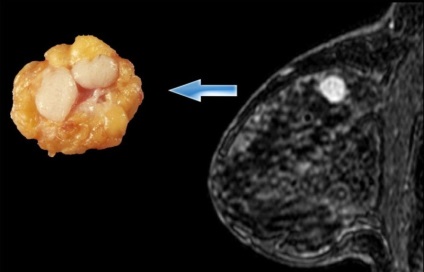

examinare pacientul începe cu inspectarea sânii folosind palparea. În plus, scanarea cu ultrasunete a sanului afectat. Exclude maligne ajută biopsie aspirației urmată de examinarea histologică a țesuturilor obținute. Dacă există îndoieli cu privire la valabilitatea diagnosticului este atribuit o mamografie plin cu raze X, o rezecție biopsie tolstoigolnaya sau tesut mamar de diagnostic cu investigații ulterioare a tumorii. Atunci când un diagnostic definitiv, ar trebui să fie eliminată boli cum ar fi cancerul de sân, formarea chistică, tsistadenopapilloma.

Fibroadenomatosis glandele mamare pot avea previziuni diferite. In unele cazuri, tumora creste rapid la o anumită dimensiune, atunci dezvoltarea sa este suspendată. Orice disconfort o femeie nu se simte. În timpul formării fibroadenoma mamare activă apar frunzelor imature. Tumora poate ajunge la 10 cm în diametru și ocupă mai mult de jumătate din piept. Datorită prezenței tumorilor mamare mari formă poate varia. In timpul sarcinii, dezvoltarea caracterului de fibroadenom devine previzibil. Acest lucru se datorează influenței hormonilor asupra țesutului glandular în care acestea cresc și să se pregătească pentru producția de lapte.